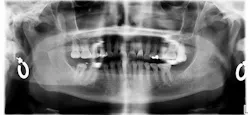

The patient presented with a history of chronic bruxism (figure 2), characterized by parafunctional clenching and grinding that wore through the enamel layer over time. Such effect stems from an increased mechanical loading on both the dentition and the temporomandibular joints, often resulting in occlusal wear, altered vertical dimension, and adaptive osseous remodeling.

A panoramic radiograph (figure 3) demonstrates evidence of a decreased posterior condylar slope, consistent with the long-term reported habit. This remodeling had altered the condylar trajectory, contributing to a collapse of the patient’s occlusal vertical dimension relative to that expected in the presence of healthy hard and soft tissues.